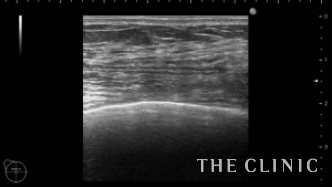

オイルと壊死した脂肪を大量に吸引し、しこりは完全になくなりました。この後CRF豊胸を行うのであれば、1ヵ月ぐらい間を空けてからすることをお勧めします。なぜかと言いますと、しこり除去後は被膜内の空間がくっつくまで待たなければ、被膜内にCRFが入る可能性があるからです。